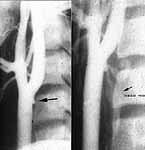

The arteriogram is shown here:

This shows four areas of filling defects consistent with intimal tears throughout the popliteal artery. The flaps moved with flow, looking like a valve. The flaps were proximally based.

Sal-- As was predictable, you did not need the arteriogram as predicted by the absence of hard signs. The injury you found is nonocclusive, of a type that may be found in about 10% of cases in the absence of hard signs, and needs no surgical Rx--as has been shown by an accumulation of 14 years of trauma, interventional radiologic and vascular literature from several centers, and without any data to refute it. You would have a hard time justifying any surgical attack on this. Certainly the limb must be monitored for any development of hard signs, and having gotten this angio (which I would not have), I would do a followup in about a week--at which time we know there is about a 90% chance it will have spontaneously resolved. Any development of hard signs, or any angiographic deterioration (extravasation or occlusion) requires surgery at that time--in which case there is no morbidity ever once yet recorded from the delay. any one may disagree with this, but like my assertion, such disagreement means nothing in the absence of supporting data that refutes the existing trove of data to the contrary.

Eric: we agree that this injury does not require surgical attack. There are nonsurgical options in my management of this injury, such platelet inhibition to decrease risks of emboli and occlusion .  Followup imaging and heightened surveillance are valuable in our experience. The orientation of intimal flaps helps predict outcome. Gently tacking the flaps back into the defects with a compliant balloon decreases the time and area of exposure of the media and perhaps decreases the risk of occlusion. Certainly popliteal occlusion has higher morbidity than nonocclusive injury.

As Eric predicted, the appearance of this injury resolved and more quickly that expected. This followup arteriogram showed no evidence of the intimal injuries present four days earlier.

I conjecture that the orientation of the flaps which were proximally based lend themselves to readherence to the exposed media.

It is when the flaps are based distally that blood flow tends to undermine and locally dissect the wall of the vessel. Surely distally based flaps can also heal but they are more likely to persist or extend.

Whether the aspirin that was administered had any effect on the rapidity of this healing process is unproven.